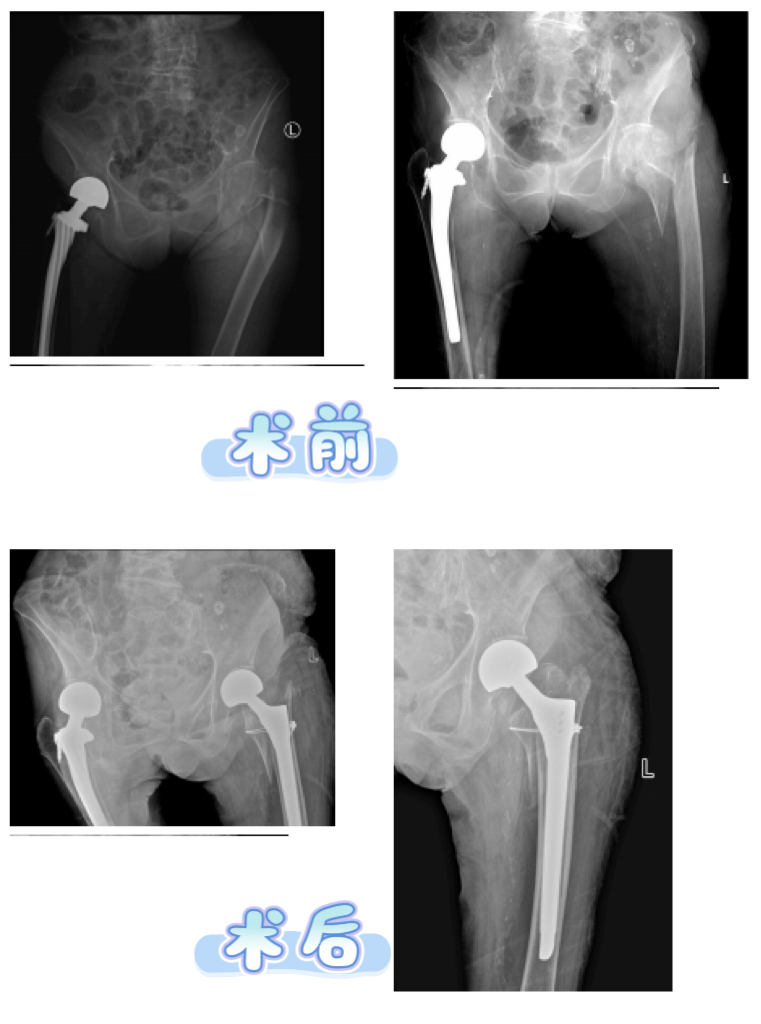

在全身状况逐步改善、各项指标趋于平稳后,手术时机终于成熟。麻醉科王仿主任团队凭借精湛的麻醉技术,为手术保驾护航,确保手术过程中患者的生命体征平稳。骨关节综合科李辉主任团队成功为张奶奶实施右侧髋关节置换术,术后患者安全返回心血管疾病诊疗中心继续接受治疗。